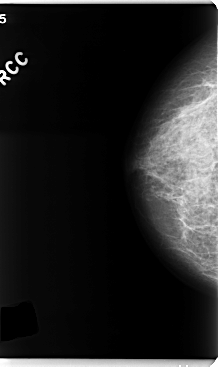

C_0193_1.RIGHT_CC

RIGHT_CC LINES 4760 PIXELS_PER_LINE 2824 BITS_PER_PIXEL 12 RESOLUTION 50 NON_OVERLAY